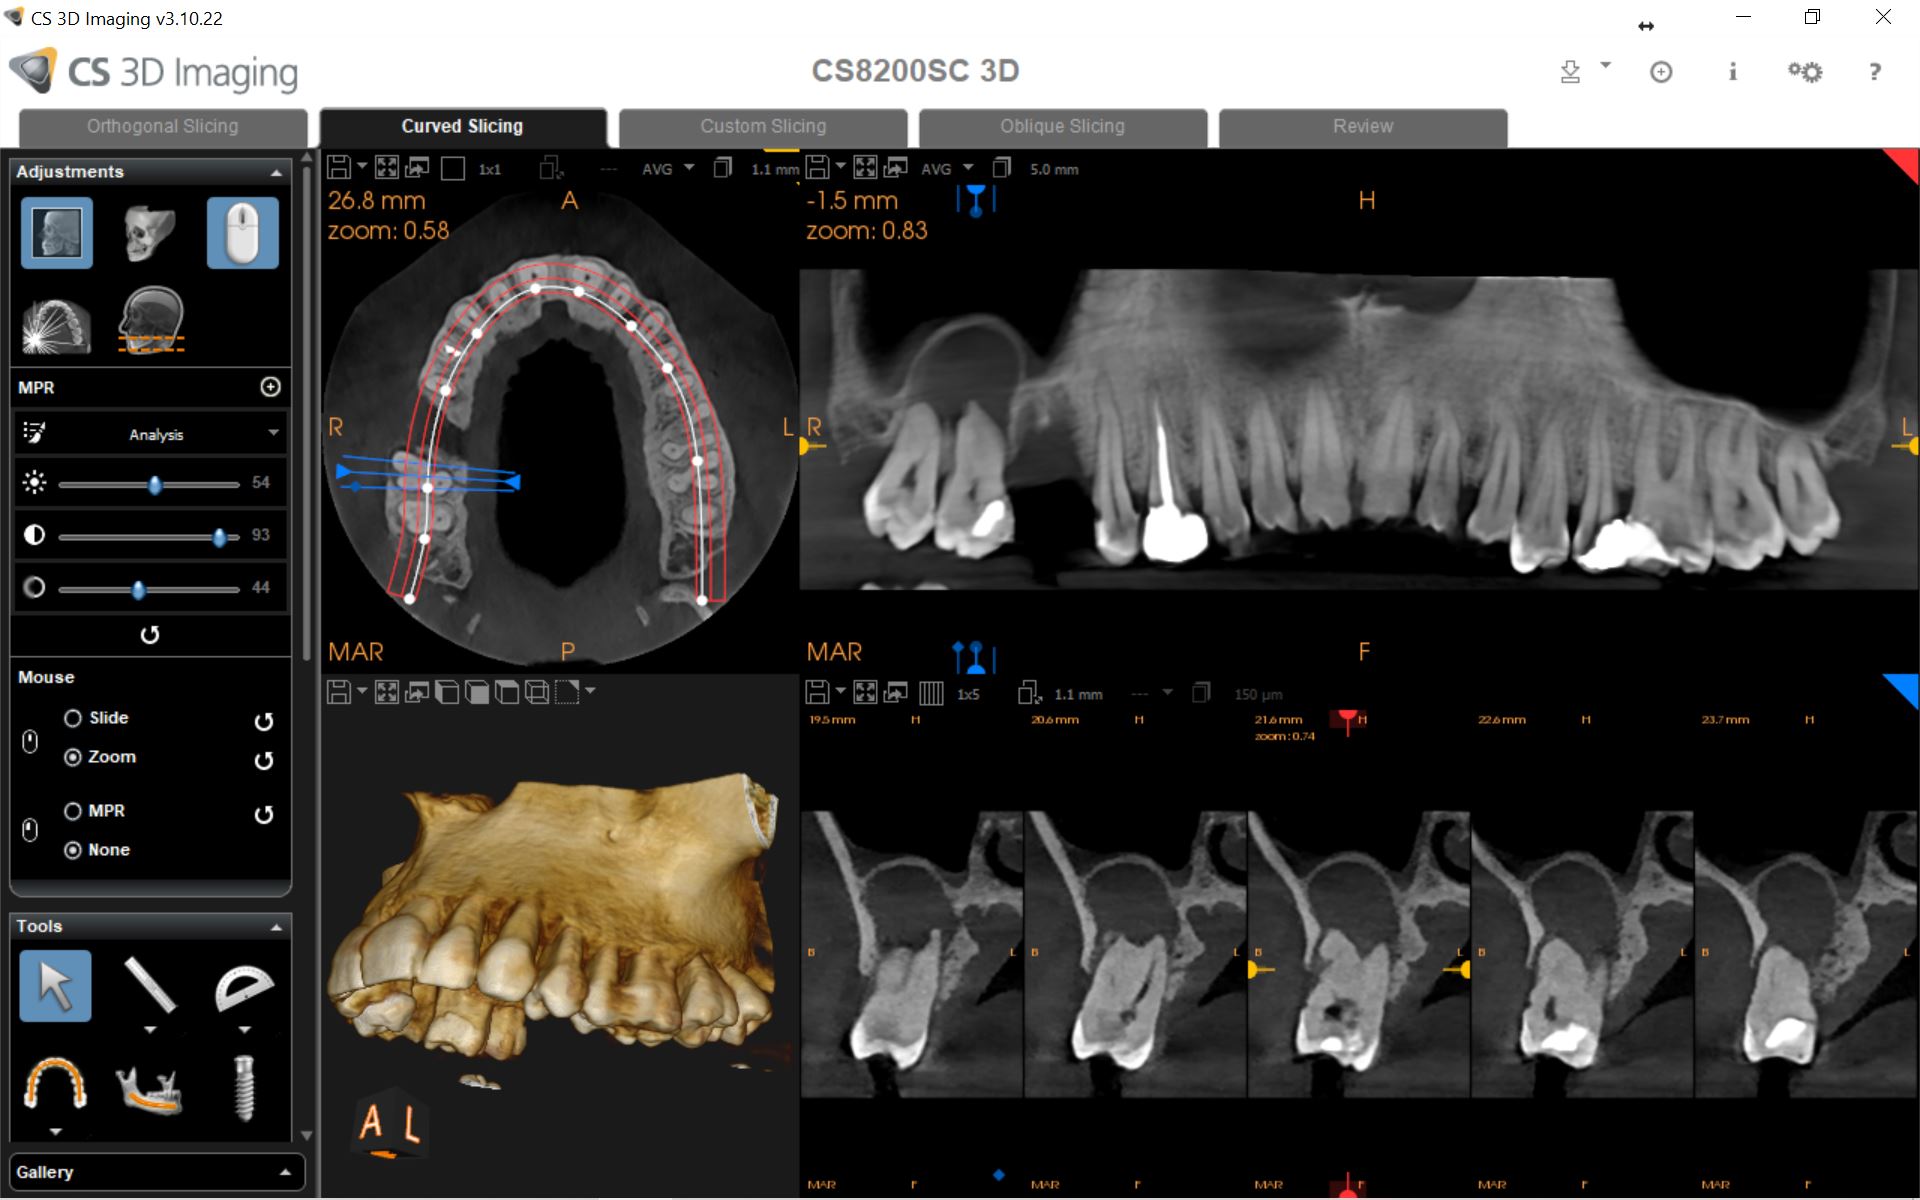

Το νέο μοντέλο CS 8200 3D Neo Edition της Carestream Dental συνδυάζει Ψηφιακή Πανοραμική με Ογκομετρικό Τομογράφο CBCT, με επιλογή εννέα οπτικών πεδίων και ανάλυση έως 75μm.

Με νέο εύχρηστο λογισμικό και ακόμα μεγαλύτερες δυνατότητες όπως το CS MAR, αλγόριθμος NAR, ανατομικά φίλτρα Endo, Perio,τεχνολογία Tomosharp, το καθιστούν ως το πιο κατάλληλο μηχάνημα για Οδοντιατρεία και Διαγνωστικά κέντρα καλύπτοντας όλο το φάσμα των απεικονίσεως οδοντογναθοπροσωπικής περιοχής με πεντακάθαρες εικόνες.